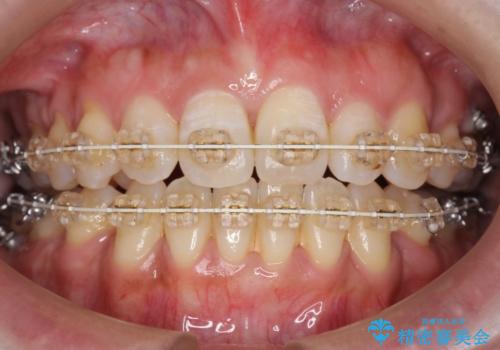

40代女性 前歯の重なり あきらめずに矯正

- 前歯の重なりを主訴に来院。

前歯が顔の真ん中に飛び出しているような状態でした。

成人の矯正でしたので、矯正治療前にしっかり必要な歯周病治療を行い、状態が改善してから開始しました。

前歯も引っ込み、口が閉じやすくなりました。